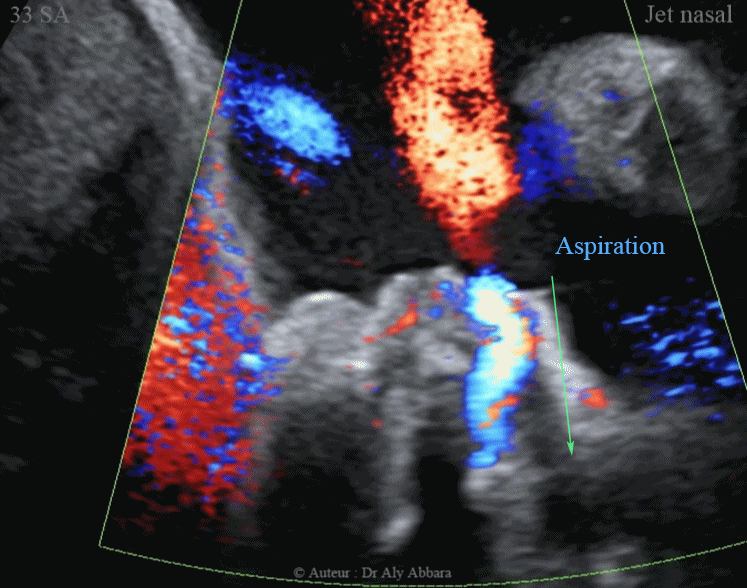

Ejection-aspiration nasales du liquide amniotique au cours des mouvements respiratoires foetaux - إدخال وإخراج السائل الأمنيوسي عبر الأنف

Images échographiques animées montrant, grâce au phénomène Doppler (Dynamic-Flow) l'éjection et l'aspiration du liquide amniotique à travers les fosses nasales au cours des mouvements respiratoires fœtaux.

Fœtus âgé de 33 SA.